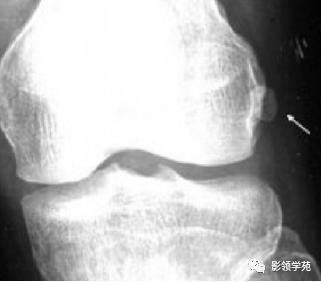

籽骨、副骨与永存骨骺一般边缘光滑, 周围皮质密度较高, 皮质光整, 附近骨质结构完整, 具有对称性, X线随诊形态及位置不会发生改变, 一般不会引起疼痛。但个别患者由于一些局部肌肉的扭伤而引起副骨的移位, 或由于机械外力的作用使副骨摩擦软组织导致滑囊炎和肌腱炎, 甚至由于长期慢性磨损可与附近正常骨质形成假关节从而产生创伤性关节炎可引起疼痛。而骨折一般具有明确的外伤史, 附近软组织肿胀明显, 疼痛症状明显, 断端锐利, 皮质断裂, 不具有对称性, X 线随诊形态及位置可发生移位。而籽骨、副骨与永存骨骺本身也可在外伤的情况下发生骨折, 但极罕见。